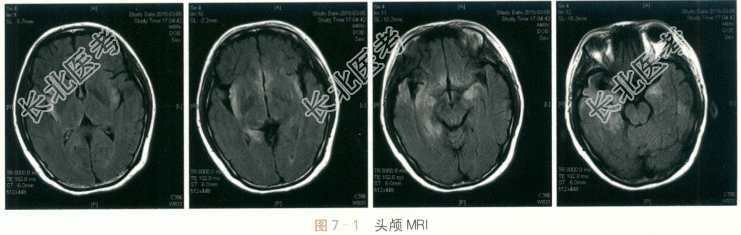

- [材料题] 患者,女性,27岁,因“发热、头痛伴精神行为异常半月余”入院。患者半月前无明显诱因下出现发热,体温最高至40℃,同时伴有头痛,以前额部持续性胀痛为主,偶有恶心呕吐,但无咳嗽咳痰、腹痛腹泻。至当地医院门诊以抗生素治疗无好转,并出现胡言乱语、烦躁不安,伴有记忆力减退及定时定向障碍,症状逐渐加重。行腰穿脑脊液中WBC160×10⁶/L,其中M074%;蛋白822mg/L,葡萄糖4.0mmol/L,氯化物122mmol/L;头颅MRI检查提示额叶、颞叶多发病灶伴有增强。予抗病毒及对症支持等治疗,患者无明显好转。1周后复查腰穿,脑脊液WBC165×10⁶/L,M055%;蛋白1008mg/L,葡萄糖2.3mmol/L,氯化物131mmol/L。为进一步诊治收住入院。自患病以来,患者胃纳可,睡眠差,大小便正常,无体重明显下降。既往史:否认肝炎结核史;否认手术外伤史;否认输血史;否认食物、药物过敏史。各系统回顾无特殊。体格检查:(1)内科检查:T37.6℃,P82次/min,BP126mmHg/81mmHg,R16次/min。双肺呼吸音清,心律齐。腹软,肠鸣音正常;肝脾无肿大。(2)神经系统检查:神清呆滞,反应迟钝,查体不合作。对答部分切题,偶有胡言乱语,定时定向差,近时记忆力减退,计算不能。颅神经:双侧瞳孔直径3mm,等大等圆,对光反射良好;眼球各方向运动正常;双侧额纹对称,双侧鼻唇沟对称,口角不偏。双侧软腭上抬可,腭垂不偏,咽反射正常。伸舌居中,无舌肌萎缩及舌肌纤颤。运动系统:四肢肌力检查不配合,四肢可见自主活动,肌张力无增减,肱二头肌反射、肱三头肌反射、桡骨膜反射、膝反射、踝反射均双侧对称(++)。双侧巴彬斯基征、戈登征(-),脑膜刺激征(-)。感觉系统及共济功能:四肢针刺觉、轻触觉、深感觉均对称正常;复合感觉检查不配合;患者共济检查不配合。脑膜刺激征:无颈抵抗;克匿征(-)。血常规:RBC4.12×10¹²/L,WBC13.5×10⁹/L,N85%;FBG4.5mmol/L。肝功能:ALT25IU/L,AST23IU/L,γ-GT27IU/L,AKP80IU/L;TB14lumol/L,DB5.3μmol/L,TP65g/L,ALB40g/L。肾功能:BUN4.4mmol/L,Cr52μmol/L。脑脊液常规:无色,透明度清,潘氏试验(+++),RBC1×10⁶/L,WBC53×10⁶/L,多核细胞17%,M083%。脑脊液生化:糖2.20mmol/L,氯123mmol/L;蛋白773mg/L;同步血糖5.50mmol/L。血清免疫学:抗核抗体、ENA抗体与ANCA均为阴性。结核试验:T-SPOT(-)。肿瘤标志物全套:均为阴性。血清病毒抗体检测:除单纯疱疹病毒Ⅰ型抗体IgG为阳性,巨细胞病毒抗体IgM、巨细胞病毒抗体IgG、单纯疱疹病毒Ⅰ型抗体IgM、单纯疱疹病毒Ⅱ型抗体IgM、单纯疱疹病毒Ⅱ型抗体IgG、EB病毒衣壳抗原抗体IgG、EB病毒衣壳抗原抗体IgM、EB病毒早期抗原抗体IgM与EB病毒抗原抗体IgG均阴性。心电图检查:窦性心律。肺部CT检查:两肺下叶炎症伴两侧少量胸腔积液;左下肺小结节影;肝门区致密影。脑电图检查:双侧见散在2~3Hzδ波、θ波;未见典型痫样放电。头颅MRI检查:双侧岛叶及右侧颞叶见片状长T₁长T₂信号,flair相呈高信号,弥散相无异常(见图7-1)。脑室系统显示可,中线结构无移位。双侧蝶窦黏膜增厚。